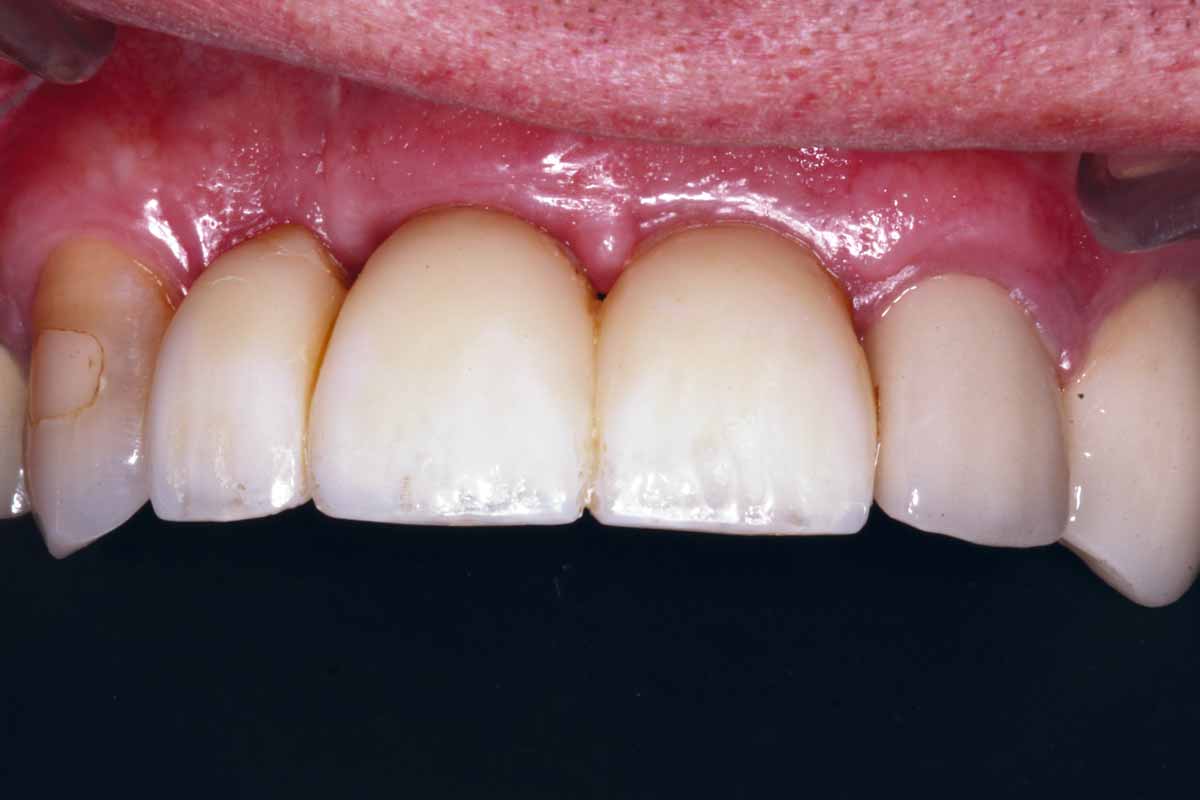

25/27 - Regeneration and maturation of the soft tissue

GBR and soft tissue augmentation with cerabone® and mucoderm® - H. Maghaireh & V. Ivancheva